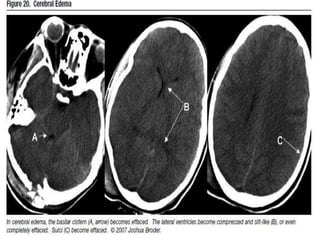

• This differentiation is loss in case of cerebral

odema.

Causes of cerebral odema

• Infection.

• Mass lesion.

• Stroke.

• Metabolic causes.

Cytotoxic

• grey-white matter differentiation is

maintained and the oedema involves mainly

white matter, extending in finger-like fashion

• secondary effects of vasogenic oedema are

similar to cytotoxic oedema, with effacement

of cerebral sulci, with or without midline shift

Vasogenic